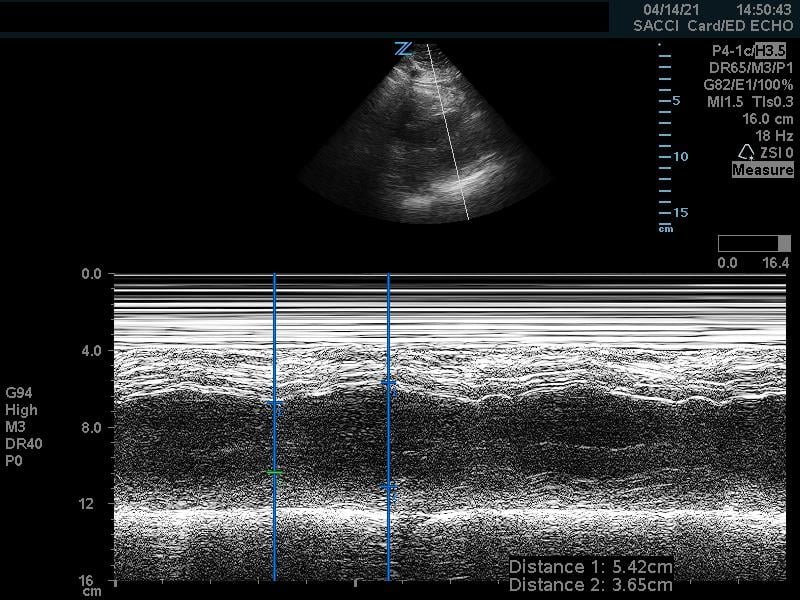

The cardiac component is essential to evaluation of a hypotensive patient as it can provide valuable information about cardiac physiology and etiology of shock. The goal of the cardiac portion of the examination is to classify presence or absence of pericardial effusion, pericardial tamponade, evaluate left and right ventricular contractility and chamber size and thus link these findings to the etiology of shock. Pericardial effusion with tamponade may be identified as a cause of obstructive shock. As fluid and pressure in the pericardial sac increases, early diastolic collapse of the right ventricular free wall is seen. (Video 1) This can be assessed visually in the parasternal long view by placing an M-mode line through the right ventricle (RV) and left ventricle (LV), including the interventricular septum and anterior leaflet of the mitral valve. (Figure 3) This allows for easy identification of right ventricular diastolic collapse, which is indicative of tamponade physiology.

Figure 3. Right ventricular diastolic collapse viewed in M-mode. Note motion of mitral valve leaflet, in the mid-field. Valve opening indicates diastole, which can then be compared to the collapse of the right ventricle in the near field.